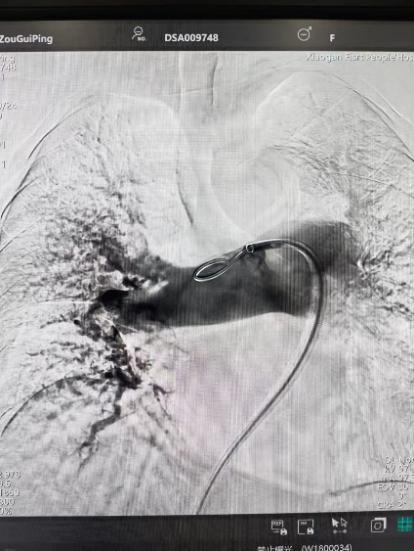

術(shù)前

手術(shù)在局部麻醉下進(jìn)行,團(tuán)隊(duì)通過股靜脈穿刺,將專用抽栓導(dǎo)管精準(zhǔn)送達(dá)肺動(dòng)脈栓塞部位,利用負(fù)壓抽吸技術(shù)成功清除大量血栓;隨后,在血栓局部精準(zhǔn)灌注溶栓藥物,進(jìn)一步溶解殘余血栓,恢復(fù)肺部血流灌注;同時(shí),為防止下肢深靜脈血栓再次脫落引發(fā)肺栓塞,團(tuán)隊(duì)為患者置入下腔靜脈濾器,整個(gè)手術(shù)歷時(shí)約1小時(shí)。術(shù)后,鄒婆婆呼吸困難癥狀即刻得到緩解,血氧飽和度顯著提升,右心負(fù)荷明顯減輕,目前身體狀況正在逐步恢復(fù)中。